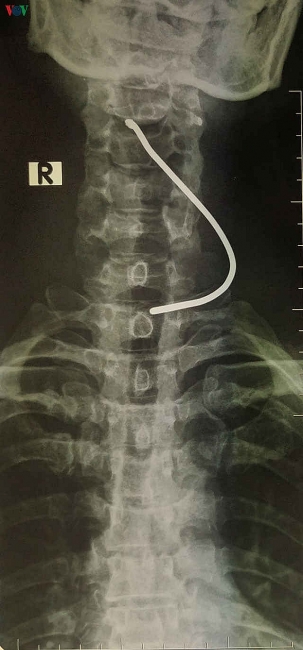

Xe ô tô nổ lốp làm bắn thanh sắt trên đường cắm vào cổ người đàn ông Một người đàn ông 50 tuổi ở Sơn Lôi, tỉnh Vĩnh Phúc đang ngồi sửa xe máy trước cửa nhà thì bất ngờ bị một thanh sắt găm vào cổ. Bạn đọc 11:55 | 26/03/2020